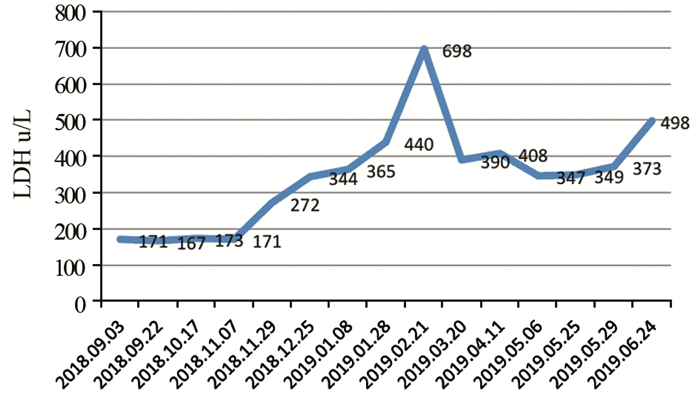

2018年9月1日患者入院接受术后辅助化疗,治疗前进行基线评估,2018年9月3日上腹CT:肝脏多发转移性病灶,见图 3。2018年9月1日乳酸脱氢酶(lactate dehydrogenase, LDH)171 u/L。依据2009版上呼吸道消化道黑色素瘤AJCC分期,患者诊断为PMME ⅣC期。因患者单肾,为保护患者肾功能,2018年9月3日、2018年9月25日开始两疗程替莫唑胺(300 mg, qd, d1~5)+恩度(15 mg, qd, d1~14)q3w联合治疗,而未加入铂类化疗,化疗后无明显不良反应。两疗程后评估,2018年10月17日胸部CT示T9、10椎体及T12密度不均匀降低,考虑转移性病变,见图 4,此时LDH 173 u/L,考虑患者出现新发骨转移,评估疾病进展(progressive disease, PD),更改治疗方案。定期行唑来膦酸骨修复治疗。

2018年10月22日、2018年11月12日开始行第一、二疗程免疫联合抗血管生成治疗:帕博利珠单抗(100 mg, d1)+安罗替尼(12 mg, qd, d1~14)q3w。治疗前检查甲状腺、肝肾功能正常,无免疫性基础疾病。治疗不良反应:骨关节酸痛,余无明显不适。两疗程治疗后进行评估,2018年11月29日LDH 272 u/L,病情评估疾病稳定(stable disease, SD)。2018年12月3日、2018年12月24日行第三、四疗程免疫加抗血管生成治疗后行疗效评估,2019年1月7日上腹部增强CT示右侧肾上腺转移性病灶,见图 5。2019年1月8日LDH 356 u/L。患者出现右侧肾上腺新发转移,肝脏病灶较前增多,病情评估PD。后患者因达到帕博利珠单抗及安罗替尼赠药,要求继续原方案治疗,2019年1月14日、2019年2月3日行第五、六疗程免疫加抗血管生成治疗,剂量同前。治疗后再次评估,2019年2月21日疗效评估PD,此时LDH 698 u/L,治疗过程中患者有反酸不适。

2019年2月22日、2019年3月22日行两疗程白蛋白紫杉醇(200 mg, d1, d8)+安罗替尼(12 mg, qd, d1~14)q3w联合治疗。不良反应:Ⅳ度骨髓抑制(中性粒细胞绝对值0.36×109/L),后行升白细胞治疗后恢复至正常水平。两疗程后疗效评估为SD。因患者出现Ⅳ度骨髓抑制,后将安罗替尼治疗剂量下调,2019年4月12日继续行第三疗程白蛋白紫杉醇(200 mg, d1, d8)+安罗替尼(10 mg, qd, d1~14)q3w联合治疗。2019年5月7日继续第四疗程白蛋白紫杉醇(200 mg, d1, d8)+安罗替尼(10 mg, qd, d1~14)q3w方案治疗,治疗后白细胞Ⅱ度降低,升白细胞治疗后恢复正常,余无明显乏力等不适反应。2019年5月29日LDH 373 u/L,疗效评估仍为SD。患者体力状况(KPS)评分80分,生活质量较好。

LDH是恶性黑色素瘤的一项肿瘤标志物。本例患者在两阶段化疗联合抗血管生成治疗中LDH水平相对平稳,并且在白蛋白紫杉醇联合安罗替尼用药过程中有下降趋势,见图 6,而在免疫治疗联合安罗替尼过程中明显升高,表明该患者对化疗联合抗血管生成治疗较免疫联合抗血管治疗显示较好的疗效。